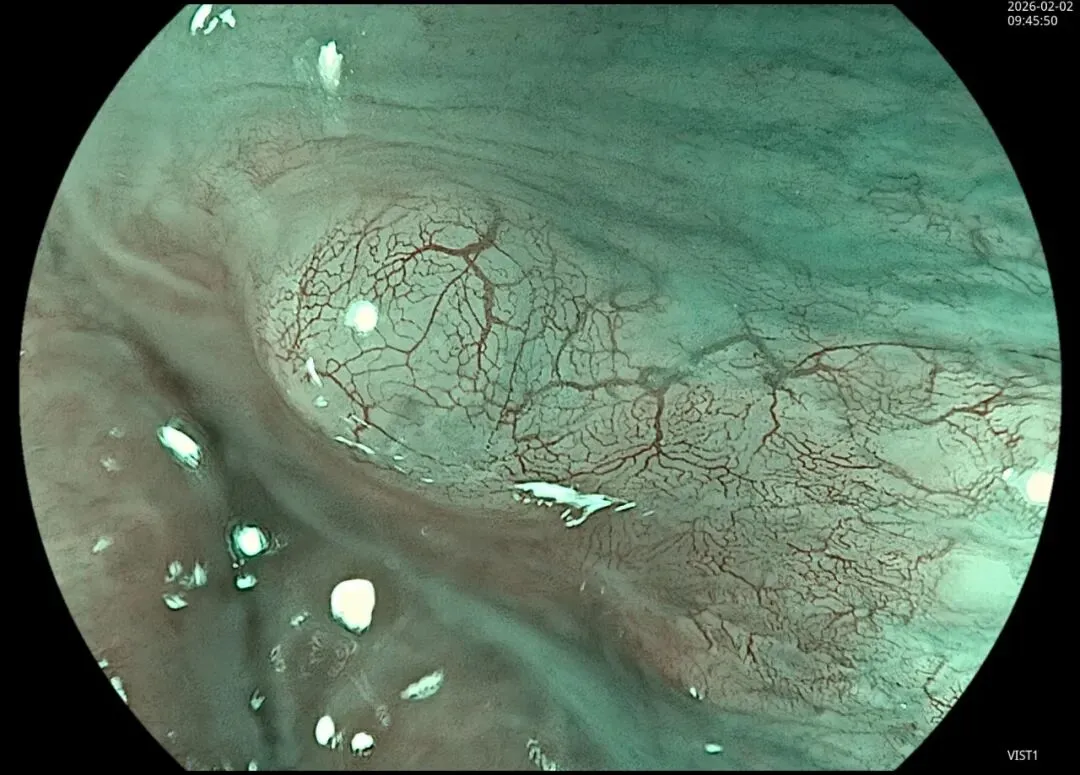

这一期不用码字,挺好的,很可惜一直没机会听过胡导讲的关于这个“花环征”的大课,学习内容来源于雨夜大师的号花环征:AIG背景的胃食管结合部的黄色颗粒状隆起及半透明“泡状”改变

补充自己在两例A型胃炎/AIG 观察到的“花环征”,巩固下学习效果。。。

2.窄带光下可见颗粒状隆起呈褐色改变,放大可见细微网状血管结构及半透明“泡状”改变